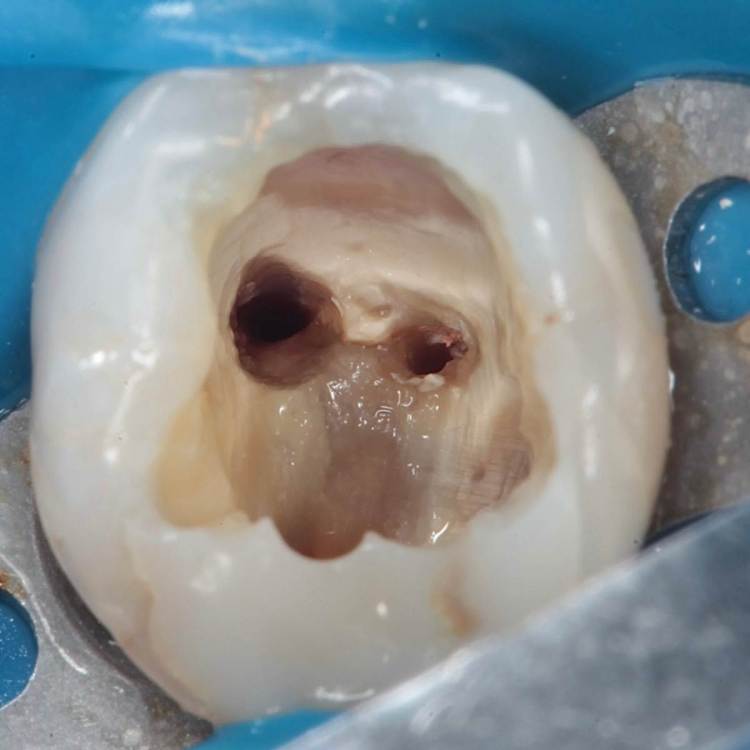

Перфорация. Симметрия каналов. Периодонтит

Как эта перфорация образовалась история умалчивает, оно и не важно, и так видно. Асимметричное расположение корневых каналов всегда наводит на мысли о неправильно раскрытом устье.

Перфорация закрыта триоксиденом, очень классный материал, и главное – наш!))

Для того чтобы при паковке триокси не провалился в каналы, они закрываются фторопластом